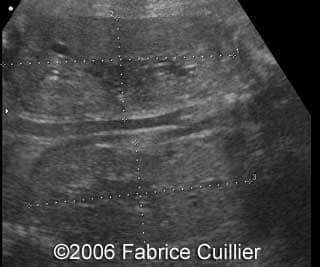

A 25-year-old woman G5P4 was referred to our hospital at 32 weeks of pregnancy due to macrosomia, ascites and bilateral nephromegaly. In her previous history there was a fetal demise after birth. The patient did not perform any screening test. There were no signs of maternal-fetal blood incompatibility. The ultrasound findings were:

- Large isolated ascites with no other signs of hydrops

- Bilateral kidney’s enlargement without increased echogenicity. The corticomedullary differentiation seemed normal

- A normal urinary bladder

- Three vessels umbilical cord

- Increased abdominal biometric parameters with subnormal other biometric parameters (around 75th percentile)

- Normal amniotic fluid level

Fetal ascites